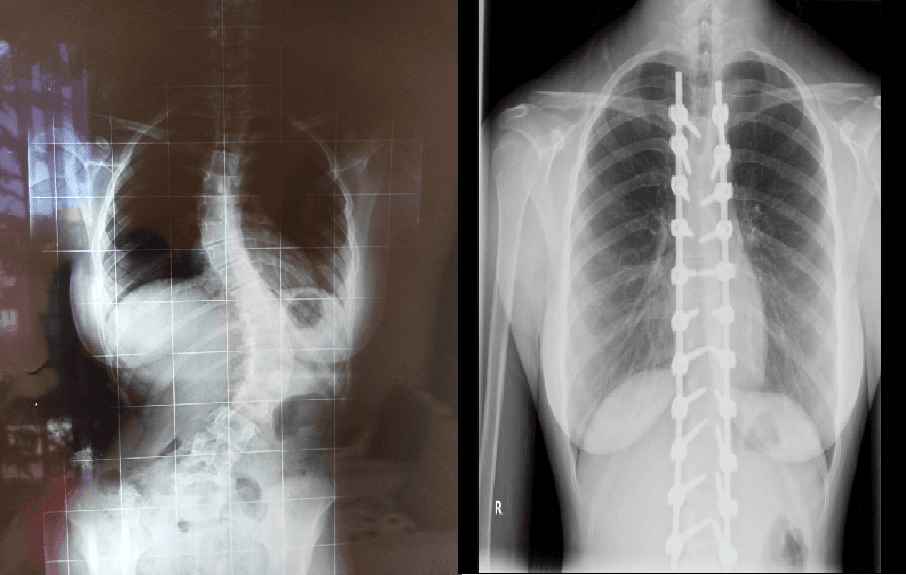

Buraya kadar çok zor ve belki de korkutucu gerçeklerden bahsettim ancak ameliyata girip çıktıktan, ailem beni saatlerce ameliyathanenin önünde bekledikten sonra her şey bambaşka oldu. Ameliyatım başarıyla tamamlandıktan sonra, ailem beni görmeden önce doktorum sayesinde röntgenlerimi gördüler ve anlattıkları kadarıyla gözlerine inanamadılar. Çünkü çok yüksek derecelerdeki eğrilikler yok olmuş, neredeyse sıfırlanmıştı, ameliyatta hiçbir komplikasyon oluşmamış ve beklediğimizden daha başarılı geçmişti. Omurgama yerleştirdikleri implantlar artık yeni en yakın arkadaşlarım olmuştu. Narkozun etkisi geçmeye başlarken ailemin yanına getirildim ve ilk olarak kollarımı bacaklarımı hareket ettirmemi izledik. Belki günlük hayatımızda farkında olmadan yaptığımız bu küçücük hareketler o sırada bizim için tüm dünyaya bedeldi. Hareket edebiliyordum. Yürüyebilecektim. Birkaç günlük yatak istirahatinden sonra ayağa kalktım. Sanki 13 yıl boyunca hiç yürümemiş gibi hissediyordum çünkü vücudumun bütün dengesi değişmişti. O gün 13 yıl sonra yeniden yürümeyi öğrendim. Tıpkı bir bebeğin ilk adımları gibi, tek başıma ilk adımlarımı atmayı öğrendim.

1 haftalık hastane sürecinin sonunda da yeniden evime geldim. Ancak evden çıkarken olduğum insanla aynı insan değildim aslında bakarsanız bir daha asla o insan olamadım. Artık hayatım boyunca benimle beraber olacak yaklaşık 30 tane implant vardı vücudumda. 3 ay boyunca her ayağa kalktığımda takmam gereken bir korse ve nasıl geçeceğini bilmediğim, geçeceğine uzun zaman inanmadığım, bazen saatlerce ağlayarak uyuyakalmama sebep olacak ağrılarım vardı. Yine de günde 15-20 dakika da olsa yapabildiğim yürüyüşler bazı şeylerin farkına varmama yardımcı oluyor, her adım attığımda gülümsememe yardım ediyordu. Nitekim günden güne ağrılarım azalmaya başladı, korseyi takmak hatta onunla yürüyüş yapmak eskisi kadar zor olmamaya ve yürüyüşlerimin süresi artmaya başladı. Bu 3 aylık sürecin sonunda ise korsemi de hayatımdan çıkarabileceğimi öğrendim ve artık implantlarımla baş başa kaldım.